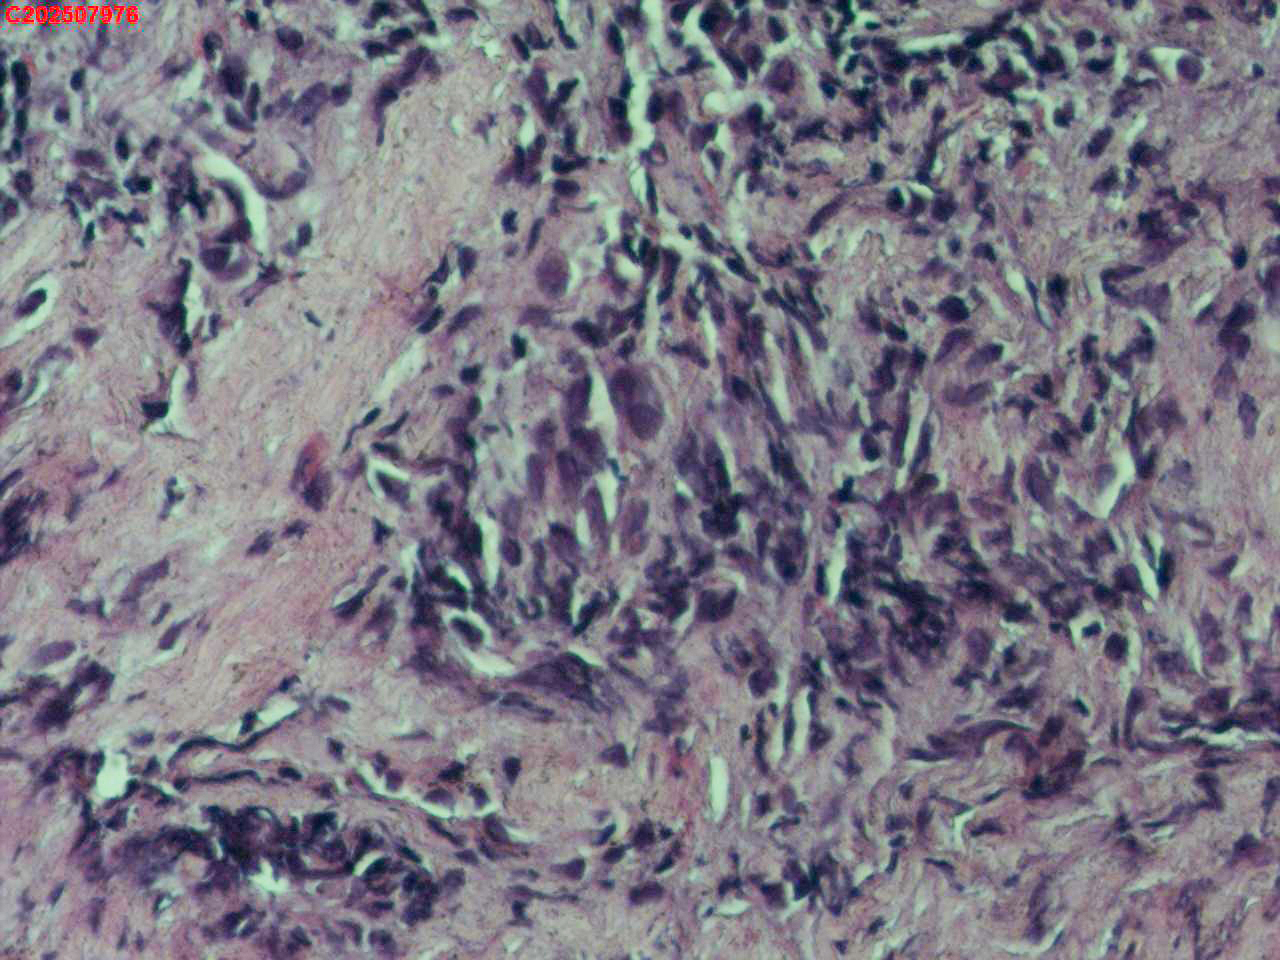

右肺上叶开口处 气管镜咬检

性别

男

年龄

65岁

临床诊断

一般病史

肺TB

标本名称

大体所见

右肺上叶开口上缘处可见肉芽增生,予咬检。

感觉:炎性纤维组织增生